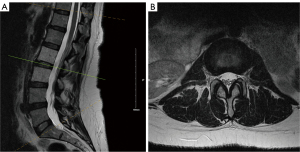

Computed tomography (CT) imaging of her spine showed an asymmetric hyperattenuating soft tissue density within the right lateral aspect of the spinal canal at the L2–3 level (Figure 1). Magnetic resonance imaging (MRI) with and without gadolinium showed a non-enhancing soft tissue signal intensity within the right lateral epidural space at L2–3 containing minimal fat signal on the pre-contrast T1-weighted images, causing mild central stenosis with mild to moderate right foraminal stenosis (Figure 2). The lack of contrast enhancement and the relatively well-defined borders made malignancy a less likely diagnosis. Epidural hematoma could not be excluded, but the heterogenous soft tissue signal in conjunction with her history of sickle cell anemia without prior trauma were less consistent. The radiographic findings were therefore suggestive of an epidural EMH lesion.